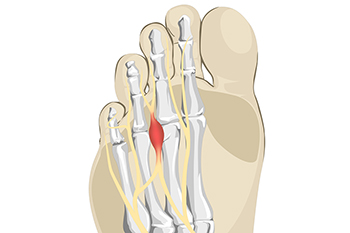

Treatment of Morton’s Neuroma

Morton’s Neuroma

Morton's neuroma is a painful foot condition that commonly affects the areas between the second and third or third and fourth toe, although other areas of the foot are also susceptible. Morton’s neuroma is caused by an inflamed nerve in the foot that is being squeezed and aggravated by surrounding bones.

What is Morton's Neuroma?

Morton’s neuroma, (also referred to as Morton’s metatarsalgia, Morton’s neuralgia, plantar neuroma or intermetatarsal neuroma) is a condition that is caused when the tissue around one of the nerves between your toes begins to thicken. This thickening can result in pain in the ball of the foot. Fortunately, the condition itself is not cancerous.

Morton’s neuroma affects women more often than men with a ratio of 4:1. It tends to target women between the age of 50 and 60, but it can occur in people of all ages. There are some risk factors that may put you at a slightly higher risk of developing the condition. People who often wear narrow or high-heeled shoes are often found to be linked to Morton’s neuroma. Additionally, activities such as running or jogging can put an enormous amount of pressure on the ligament and cause the nerve to thicken.

There usually aren’t any outward symptoms of this condition. A person who has Morton’s neuroma may feel as if they are standing on a pebble in their shoe. They may also feel a tingling or numbness in the toes as well as a burning pain in the ball of their foot that may radiate to their toes.

In order to properly diagnose you, the doctor will press on your foot to feel for a mass or tender spot. He may also do a series of tests such as x-rays, an ultrasound, or an MRI. X-rays are usually done to rule out any other causes for your foot pain such as a stress fracture. Ultrasounds are used to reveal soft tissue abnormalities that may exist, such as neuromas. Your podiatrist may want to use an MRI in order to visualize your soft tissues.

There are three main options for treatment of Morton’s neuroma: Injections, decompression surgery, and removal of the nerve. Injections of steroids into the painful area have been proven to help those with Morton’s neuroma. Decompression surgery has been shown to relieve pressure on the affected nerve by cutting nearby structures such as the ligaments in the foot. Another treatment option would be to surgically remove the growth to provide pain relief.